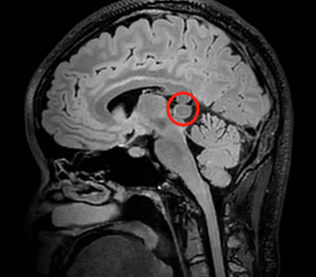

再次头部增强核磁检查,松果体区发现一个异常信号,这究竟又是什么?为何一直保持沉默的它,能够让一个原本健康的女孩突然陷入昏迷?小野的脑瘤恰好长在松果体区,松果体区位于大脑的中心位置,靠近第三脑室后部和中脑导水管。这一区域是脑脊液循环的关键通道之一。松果体区肿瘤的生长会直接压迫或阻塞这些结构,影响脑脊液的正常流动。这种梗阻性脑积水会引起颅内压升高,导致头痛、呕吐、视力障碍(如视乳头水肿)和神经功能恶化等症状。

INC巴教授在为小野评估时也提到:“众所周知,这种病变可以引起暂时性的脑脊液梗阻,这种梗阻很可能引起昏厥和抽搐(但不是癫痫发作)。手术是必要的,因为大脑导水管梗阻导致脑脊液阻塞,会引起暂时性颅内压升高。手术的最佳时机是越早越好。”